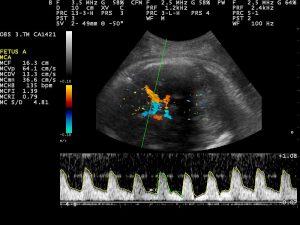

No exame de ultrassom com doppler é possível visualizar através de um mapeamento completo do corpo para observar se existe algum comprometimento no fluxo sanguíneo, em qualquer parte, menor que seja.

Devido aos altos riscos, esse método só é recomendado quando constatado que a banda amniótica está envolvendo uma grande parte do corpo do feto, como um braço inteiro ou uma perna. Nesse caso, o exame de doppler é fundamental para se observar o fluxo sanguíneo do membro envolvido e se estudar as possibilidades e real necessidade do procedimento.